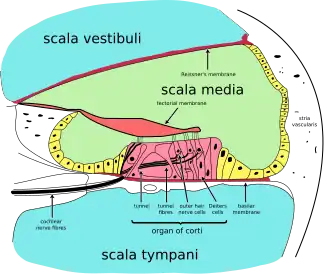

| Cross section of the cochlea. | |

Outer hair cells (OHCs) contribute to the structure of the Organ of Corti, which is situated between the basilar membrane and the tectorial membrane within the cochlea (See Figure 3). The tunnel of corti, which runs through the Organ of Corti, divides the OHCs and the inner hair cells (IHCs). OHCs are connected to the reticular laminar and the Deiters’ cells. There are roughly twelve thousand OHCs in each human ear, and these are arranged in up to five rows. Each OHC has small tufts of 'hairs', or cilia, on their upper surface known as stereocilia, and these are also arranged into rows which are graded in height. There are approximately 140 stereocilia on each OHC.[13]

OHCs are different in that they actually contribute to the active mechanism of the cochlea. They do this by receiving mechanical signals or vibrations along the basilar membrane, and transducing them into electrochemical signals. The stereocilia found on OHCs are in contact with the tectorial membrane. Therefore, when the basilar membrane moves due to vibrations, the stereocilia bend. The direction in which they bend, dictates the firing rate of the auditory neurons connected to the OHCs.[14]